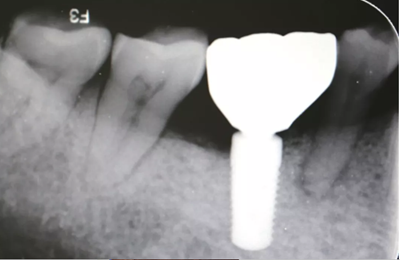

16、修復(fù)前根尖片

二期術(shù)后1月根尖顯示種植體周圍骨質(zhì)穩(wěn)定,無進(jìn)一步吸收。

(2018年5月25日)

修復(fù)完成6周隨訪,根尖片示種植體骨結(jié)合穩(wěn)定,沒有進(jìn)一步骨吸收。

(攝于2018年7月27日)